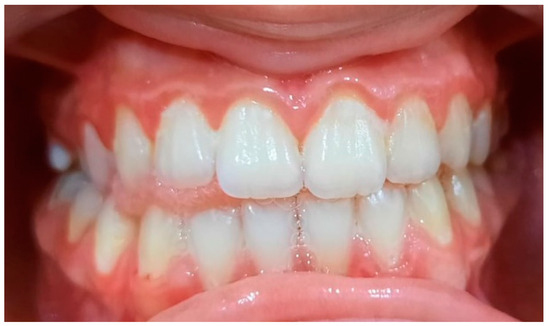

2.2. Clinical Examinations

3.2. Analysis of Clinical Data